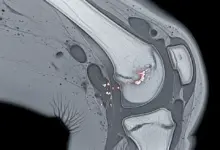

A condromalácia patelar envolve desgaste ou amolecimento da cartilagem na região da patela.

Em muitos casos, o exame físico detalhado pesa tanto quanto a ressonância.

O joelho precisa ser analisado como um conjunto, porque cartilagem, alinhamento, musculatura e padrão de movimento interferem diretamente no resultado.